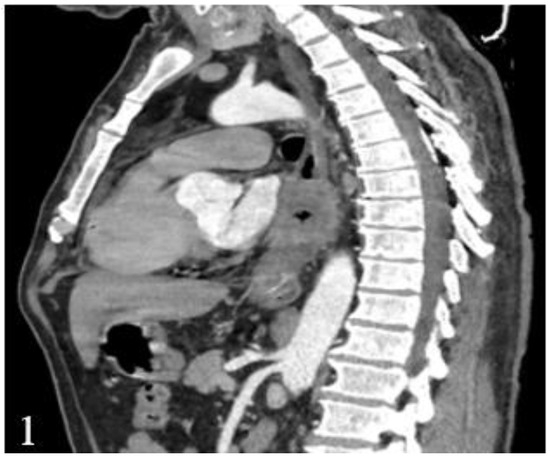

Figure 1.

Postcontrast CT, arterial phase, sagittal plane. Circumferential marked parietal thickening of the distal thoracic esophagus and gastroesophageal junction with heterogeneous structure that generates stenosis.